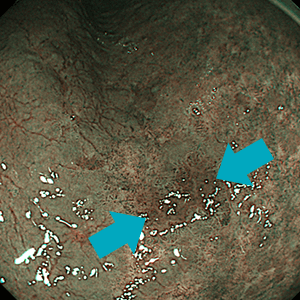

早期食道がん(右のNBI観察では明瞭化)早期食道がん(右のNBI観察では明瞭化)